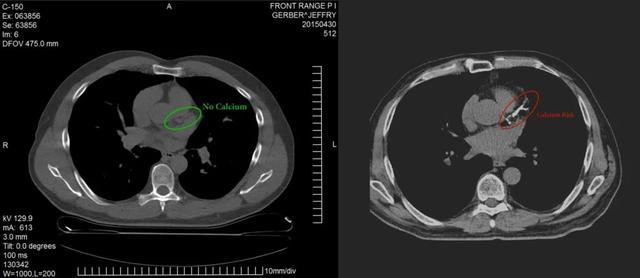

左侧来自Jeffry N. Gerber , 右侧为其他人的对比图

15年低碳生酮饮食 , CAC评分为0

他的身体状况和血脂状况都很好 , 为了再进一步确认 , 他也做了CAC扫描 , 结果发现:他的CAC评分为0 。

医学博士Jeffry N.Gerber , 一直在坚持低碳生酮饮食 , 并且持续了15年之久 。